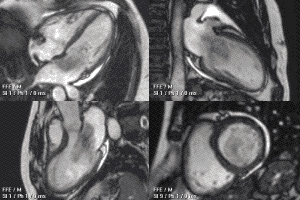

心脏功能电影成像

心肌的电影图像可以利用实时CMR成像技术得到,但此方法图像质量有限。最普遍的方法是通过使用心电门控及k-空间分段采集方法,在多个心动周期内来获得一个心动周期每个阶段的图像。该技术形成了利用CMR进行心脏功能评估的基础。这些方法产生的是亮血图像,其中的(亮)血与(黑)心肌之间的对比度可以帮助区分血和心肌。此技术通常会采用平衡稳态自由进动(SSFP)序列,亦被称为TrueFISP、b-FFE或Fiesta,不同的厂商对它有不同的称呼。

利用SSFP得到的四腔心图像